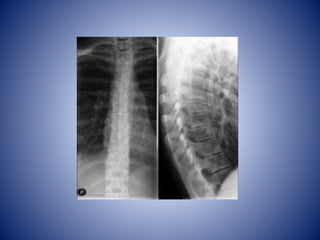

RAQUIS

COLUMNA VERTEBRAL

• Se extiende desde el cráneo hasta el vértice

del cóccix

• Es la parte principal del esqueleto axial

• Adultos mide de 72 a 75 cm de longitud

• ¼ parte de la longitud se debe a los discos

fibrocartilaginosos

CURVATURAS C.V

• Un adulto posee 4 curvaturas

• Otorgan un soporte flexible con la elasticidad

necesaria para absorber los choques.

• Curvatura torácica y sacra: concavidad

anterior

• Curvatura cervical y lumbar: concavidad

posterior